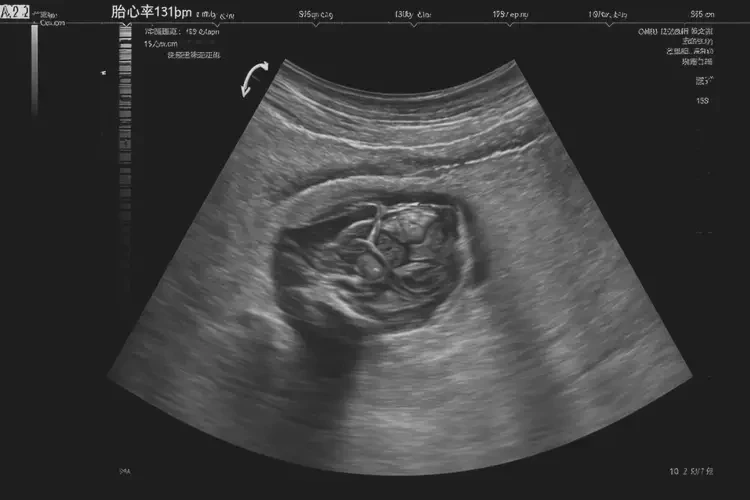

胎心131次/分钟在孕15周3天属于正常范围。

胎心率是指胎儿心脏每分钟跳动的次数,是评估胎儿健康状况的重要指标之一。在孕15周3天,胎儿的胎心率通常在120-160次/分钟之间波动,因此131次/分钟的胎心率在这个时期是正常的。